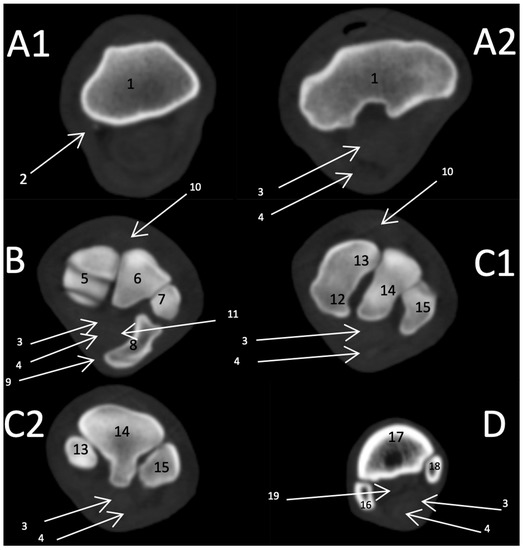

3.2. CT Findings

3.2.1. Sagittal and 3D Scan

3.2.2. Transverse Scan